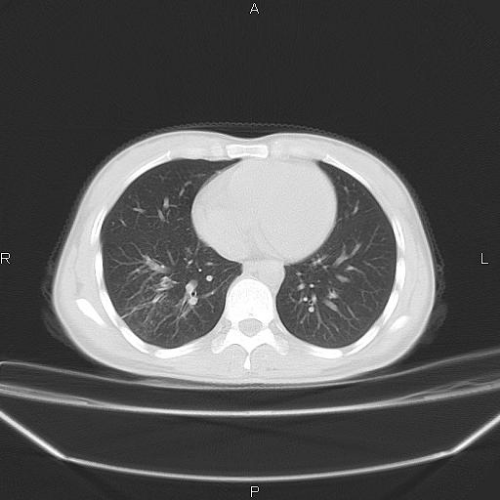

CT49877:肺部

女 30岁,半月前发热39度,血沉71,抗炎治疗半月,一直下午低热37.5

斜裂好像在前面吧 首诊一般先考虑炎症性病变

病灶在叶间裂位置,而且密度也不怎么高,所以我考虑是叶间积液,但看病史像是结核,还是做个痰检再确诊。

结核?查查别处

结合病史考虑结核

支持结核灶

结核灶